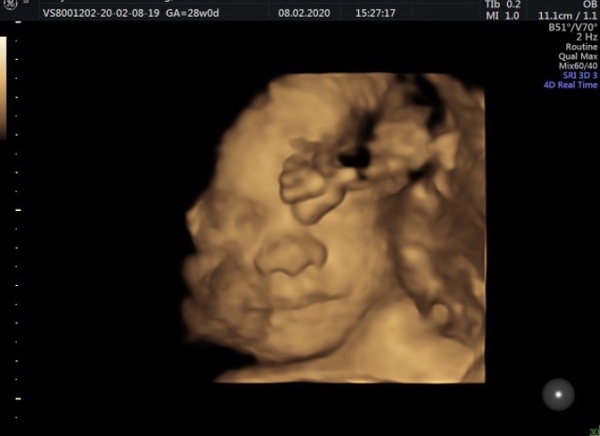

Hope you don’t mind me sharing this pic of baby, I’m just so in love with her already 🥰 makes it seems so so real now, she’s an actual little person 😍 and yes she does have her foot in her face! Little gymnast in the making x

@Sunshine8888 that picture is precious!

@Sunshine8888 oh she’s gorgeous, what a great picture, 4D ones aren’t always as clear as that!